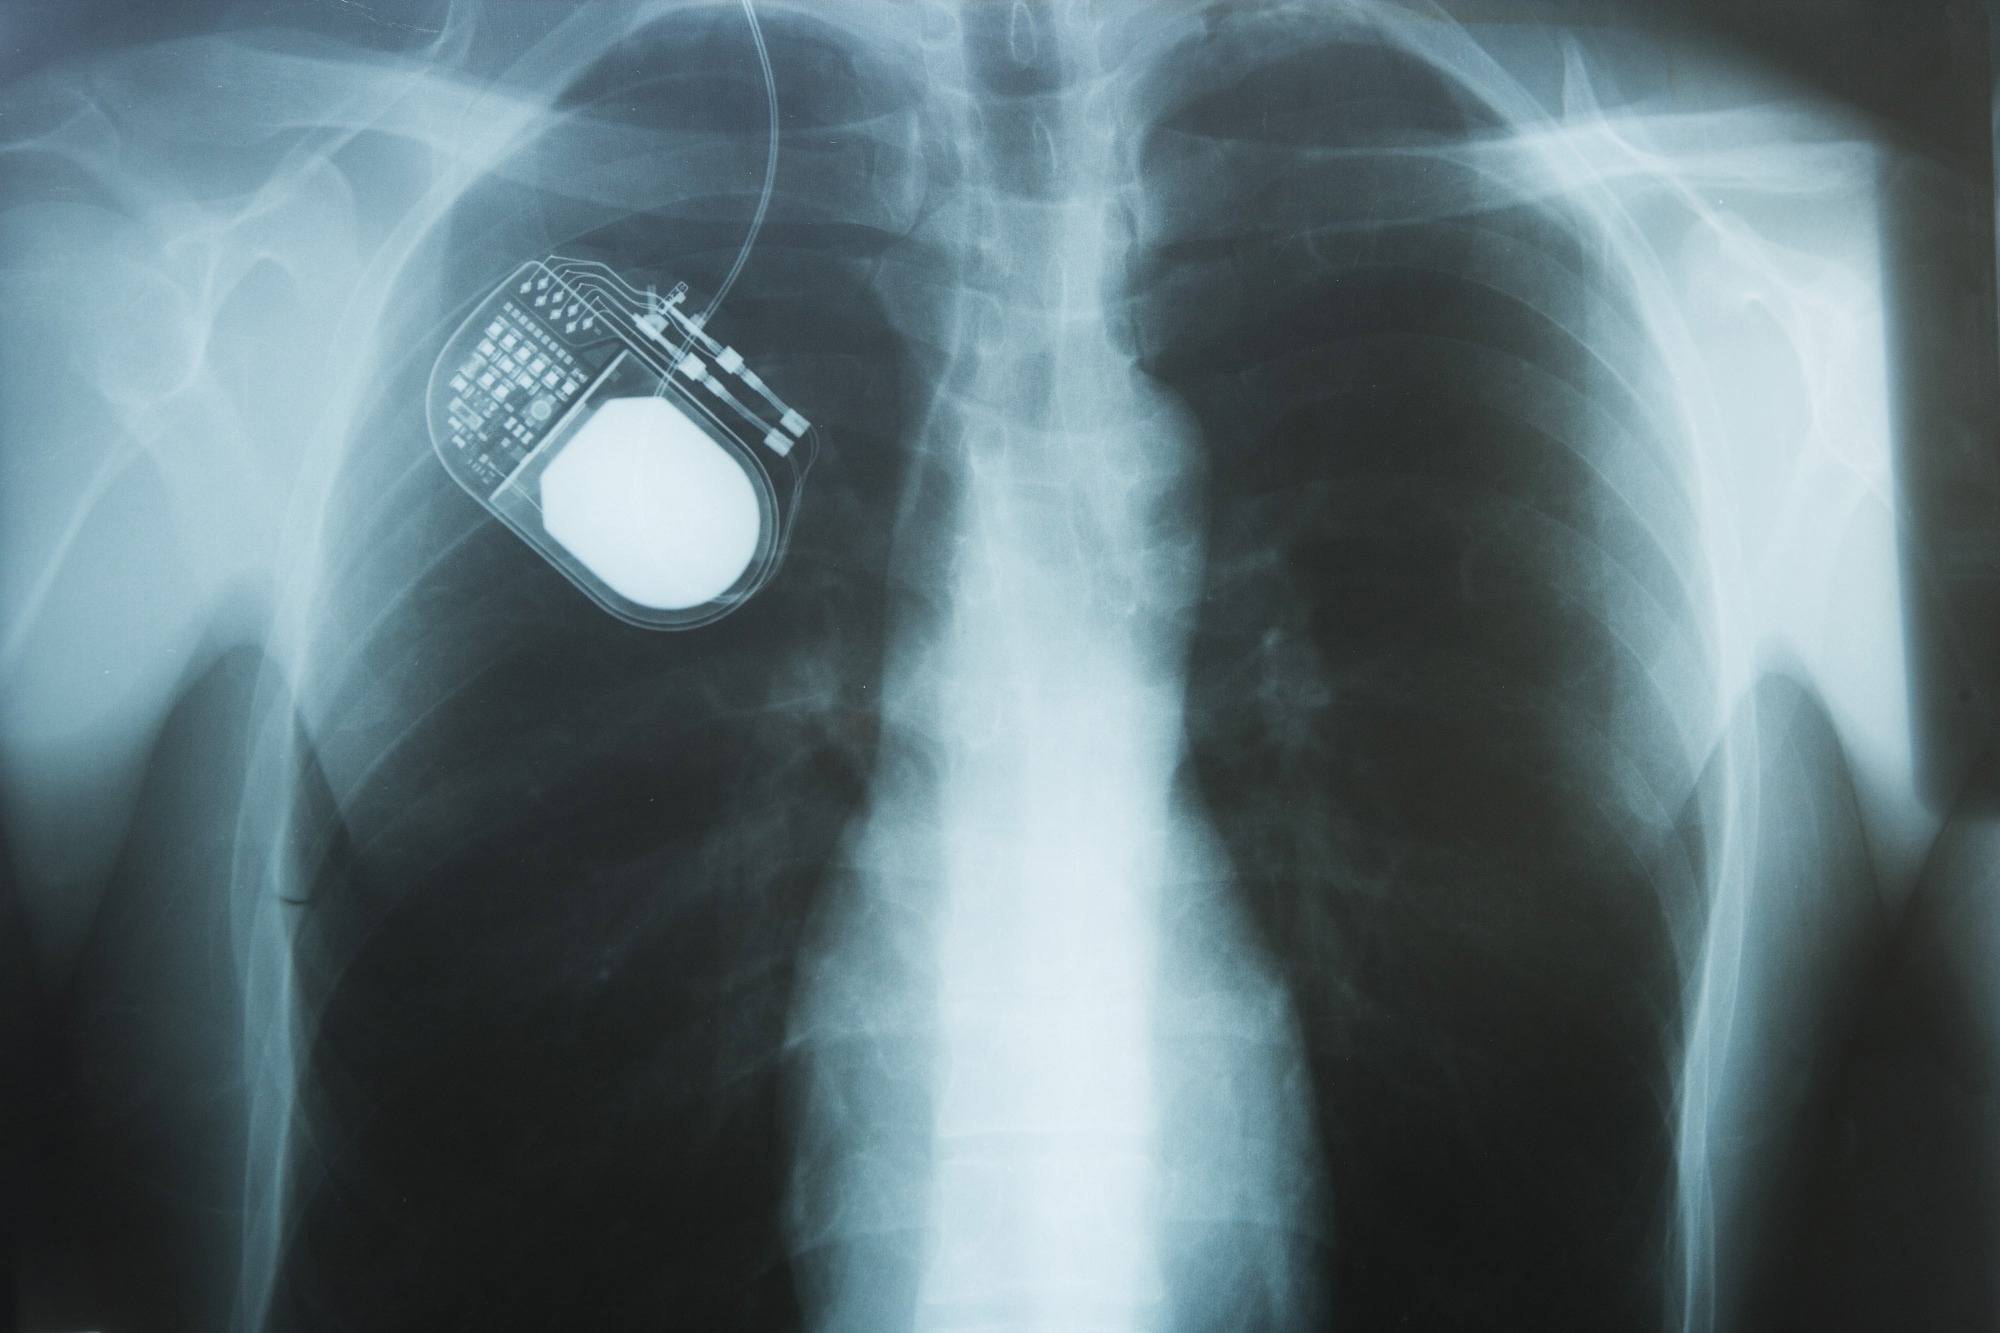

Nerve simulator on chest X-rayImage credit: Image Point Fr/Shutterstock.com

Since its FDA approval in the late 1990s, deep-brain stimulation (DBS) has become one of the most common surgical treatments for Parkinsons disease (PD), widely used for patients with advanced motor symptoms1. The procedure involves implanting electrodes into specific brain regions connected to a pulse generator beneath the collarbone. Electrical impulses alter neural activity, reducing tremors, stiffness, and bradykinesia, and restoring balance to the brains electrical circuits.